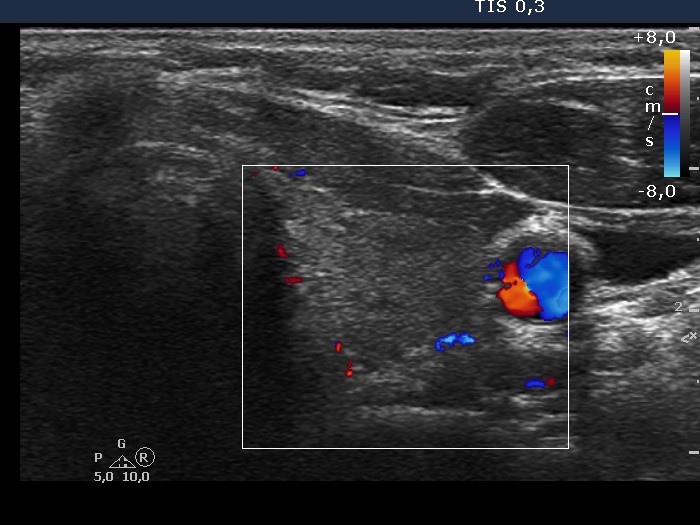

Lymphocytic thyroiditis - case 1137 (ultrasonographic picture 6)

Left lobe, transverse view, color Doppler mode. The vascularization is decreased.